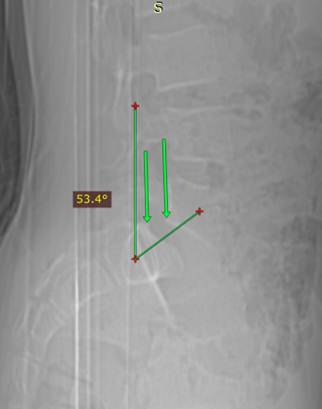

Основную

информацию несет боковая рентгенограмма. Обращают внимание на соотношение 1

крестцового и пятого поясничного позвонков: задние края их тел должны находится

строго друг над другом, на одной вертикали. Обратите внимание, не передние, а

именно задние! Так определяется соскальзывание пятого поясничного позвонка с

крестца, называемое спондилолистезом.

особенностей. Рентгенография поясничного и крестцового отделов позвоночника

выявила спондилолистез пятого поясничного позвонка первой степени. Отмечается

достаточно широкое просветлелние в межотростчатой зоне дужки 5 поясничного

позвонка и его spina bifida. Выполнена РК - томография пояснично – крестцового сочлениения,

КТ

– эмуляция рентгенограммы и снимок с КТ – томограммы вышеописанного больного.

На боковом снимке поясничного и крестцового отделов позвоночника отчетливо

виден спондилолистез: задние края 5 поясничного и 1 крестцового позвонков

обозначены стрелками, видно смещение 5 поясничного позвонка вперед в пределах 1

четверти ширины тела первого крестцового

позвонка (1 степень по Меердингу). Угол Митбрейта 53° - значительно увеличен. На аксиальном скане 5